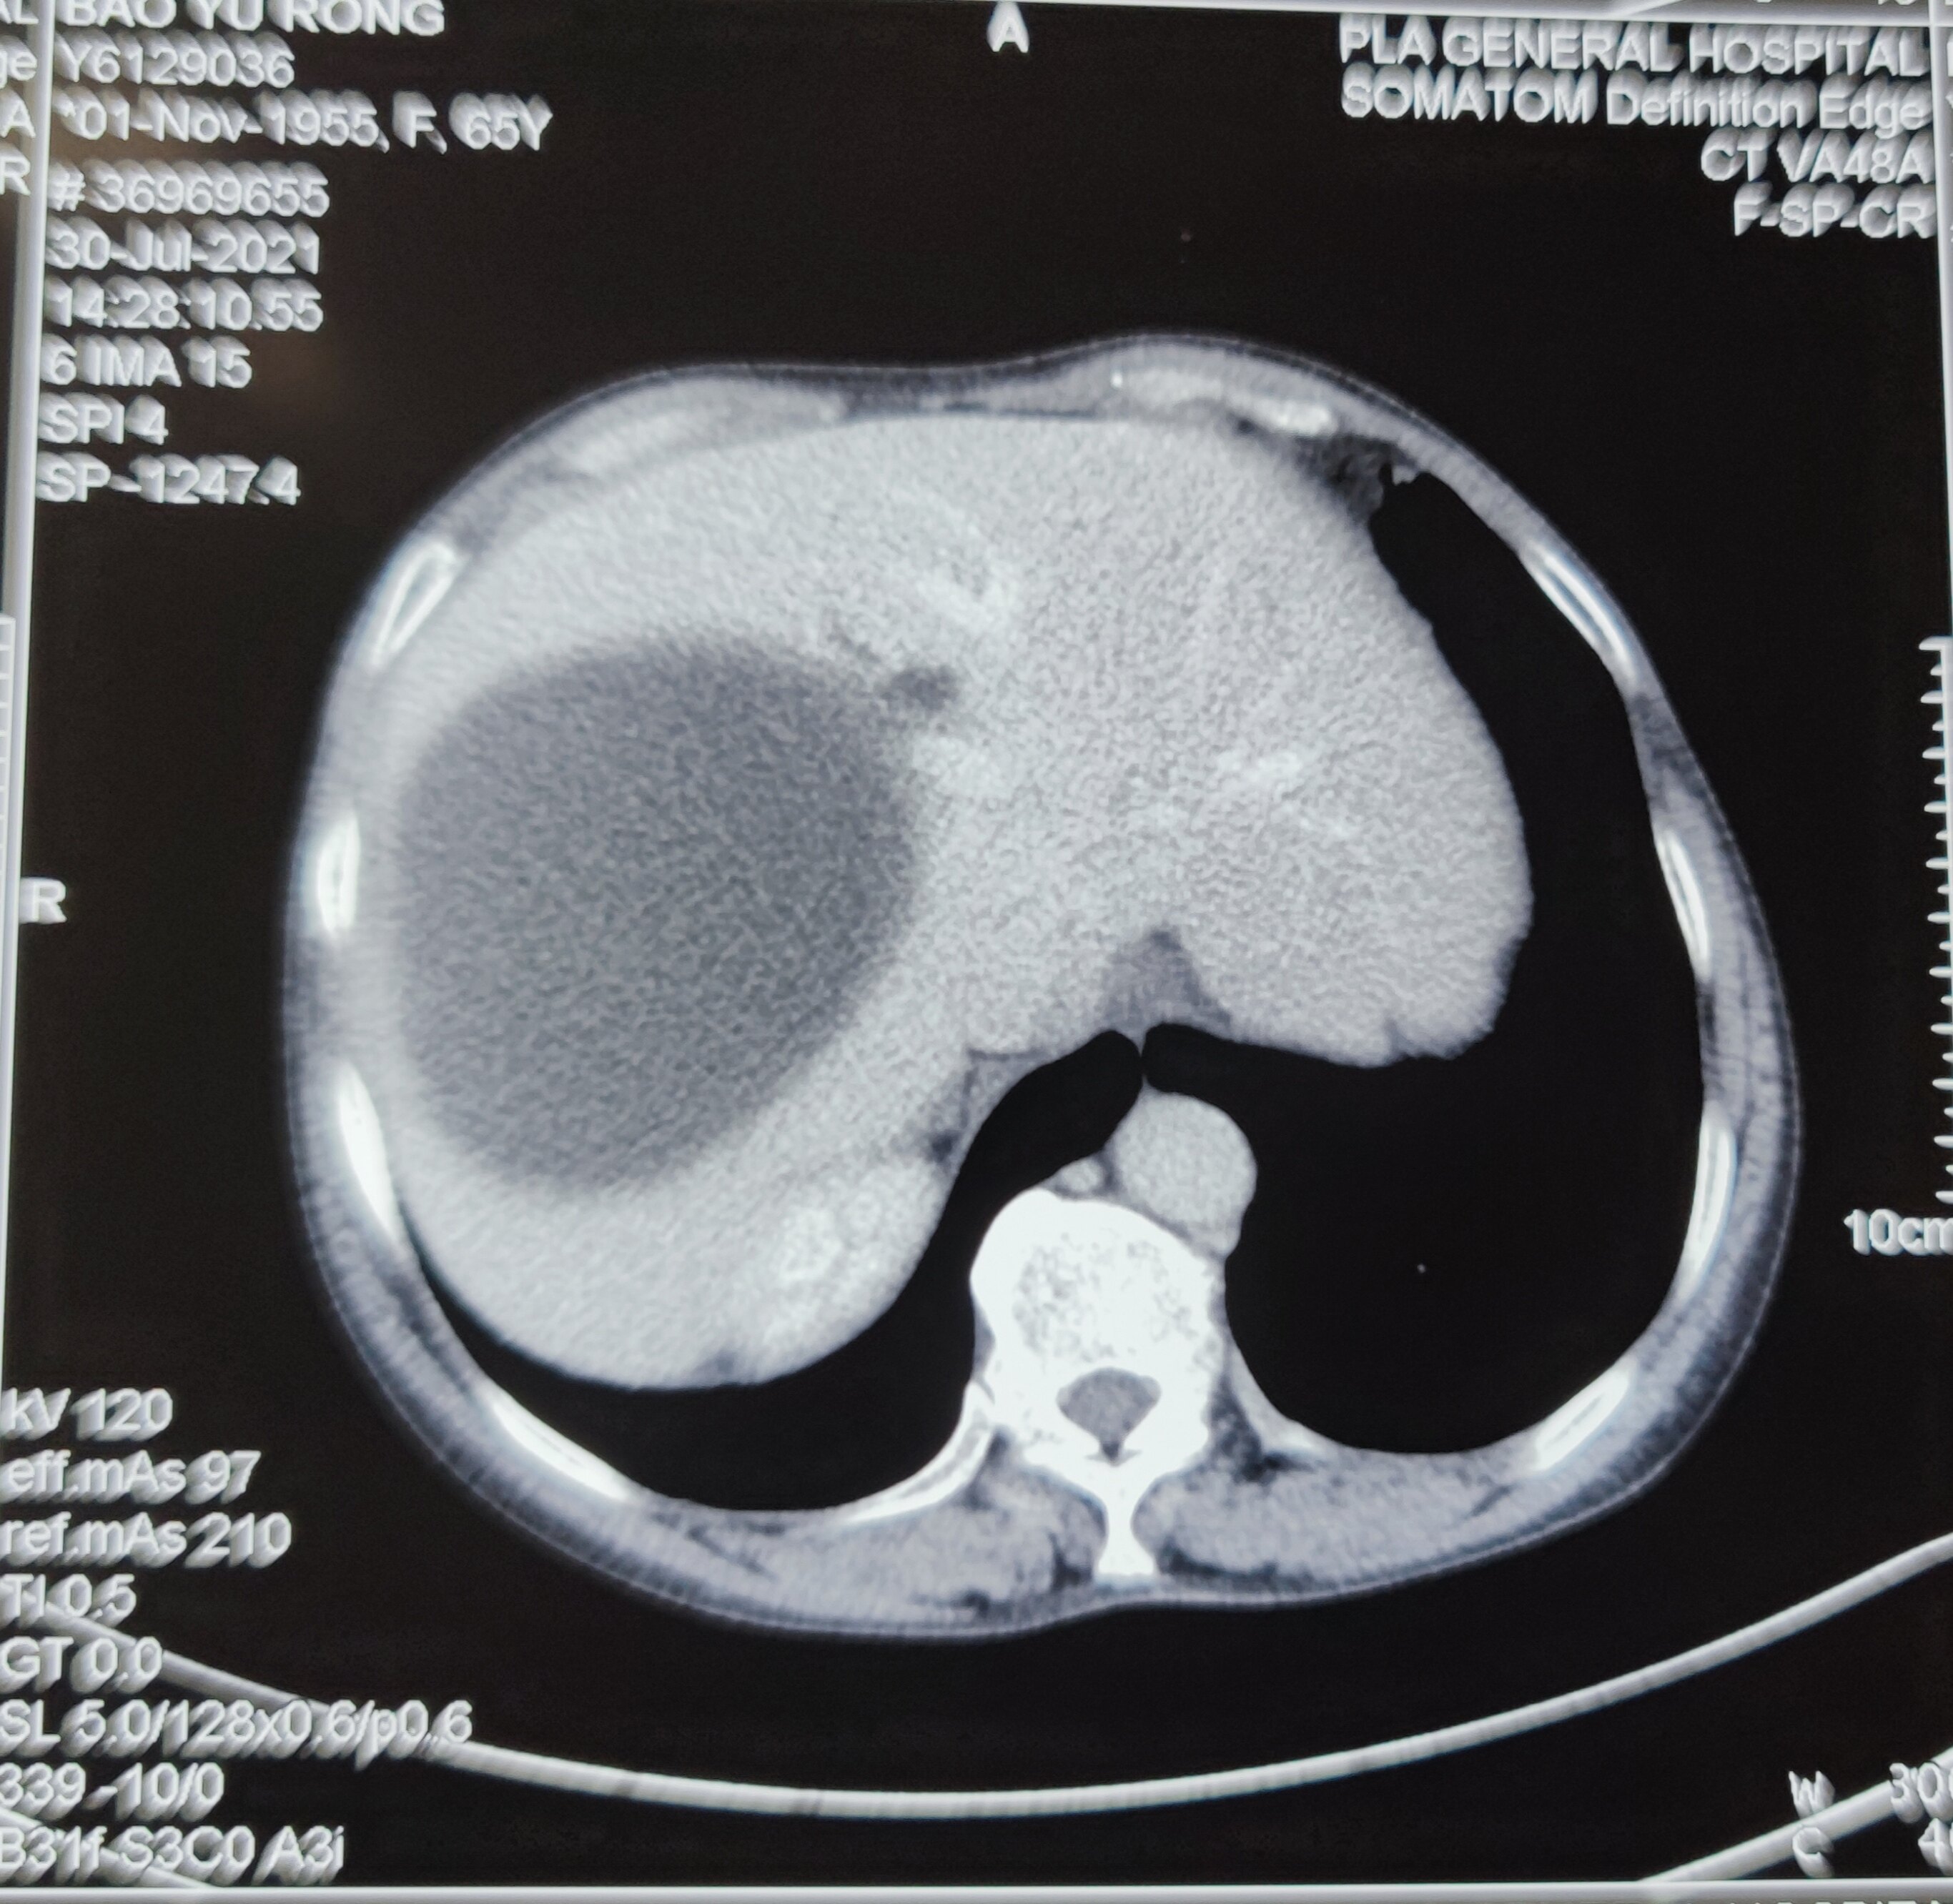

大约有10%左右的人都有肝囊肿,有些人一旦检查出肝囊肿,误认为这也是种瘤子,十分害怕,其实不对,肝囊肿不是肿瘤,是一种良性的囊性结构。 肝囊肿,通俗点说就是肝脏中的“水泡”。绝大多数的肝囊肿都是先天性的,即因先天发育的某些异常导致了肝囊肿形成。后天性的因素少有,如在牧区,如人们染上了包囊虫病,在肝脏中便会产生寄生虫性囊肿。外伤、炎症,甚至肿瘤也可以引起肝囊肿。囊肿可以是单发的,就只一个,小至0.2厘米;也可以多到十来个、几十个,甚至也可有一个是大至几十厘米的。多发性肝囊肿病人有时还合并其他内脏的囊肿,如伴发肾囊肿、肺囊肿及偶有胰囊肿、脾囊肿等。多囊肝的囊肿可满布肝脏,有些病人常以上腹肿块为首发症状,终末期出现腹水,门脉高压等肝功能不全的症候。肝囊肿一般是没有症状的。当囊肿长大到一定程度,可能会压迫胃肠道而引起症状,如上腹不适饱胀;也有因囊肿继发细菌感染而有腹痛、发热的。随着影象诊断学的发展及普及,尤其是B超已列为人群体格检查的常规之一,而B超对肝囊肿的检出率可达98%,所以发现本症的不少。在人们的心目中,囊肿是在肝脏上面长出来的一个肿瘤,尽管没有多大的症状,也很不放心,会不会变肝癌呢?肝囊肿常见的并发症是破裂出血、细菌感染、瘘及穿透,而罕见癌变。先天性肝囊肿是绝对不会癌变的。

肝囊肿是一种较常见的肝脏良性疾病,可分为寄生虫性、非寄生虫性和先天遗传性。

肝囊肿病因大多数系肝内小胆管发育障碍所致,单发性肝囊肿的发生是由于异位胆管造成。肝囊肿生长缓慢,所以可能长期或终生无症状,其临床表现也随囊肿位置、大小、数目以及有无压迫邻近器官和有无并发症而异。

肝囊肿与肿瘤是完全不同的两个概念。囊肿是液性占位,而肿瘤是实质性占位。一般说,在B超下,囊肿与肿瘤很易鉴别。应该警惕的是,肝囊肿与肝癌可合并存在,肝癌伴发肝囊肿并非罕见。因此,临床医生不要满足于肝囊肿的诊断?;褂κ笨瘫3侄愿伟┑木栊?,为此,发现有肝囊肿者,一不要忘记检测血AFP,因为60%-70%的原发性肝癌患者AFP升高。二是应到正规医院或找有经验医生行超声波检查,必要时可加作CT扫描检查。